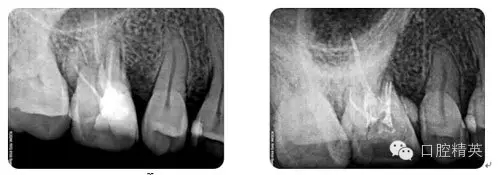

病例1:常規(guī)根管治療

病例2:各型MB2根管